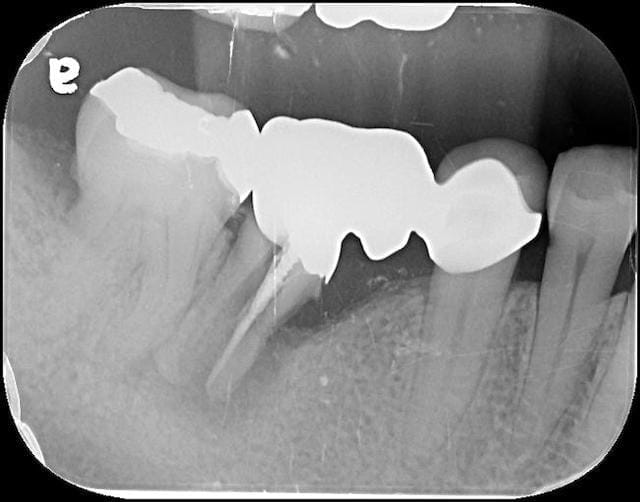

圖示:針對Mrs.Hsieh不適部位拍攝的局部X光片

雖然她的症狀跟牙周病有點類似,但我們在局部的X光片可以明顯看到她右下的大臼齒牙根已經明顯有縱向斷裂。通常這樣細菌會累積在裂縫處,造成局部牙齦發炎和齒槽骨破

壞,找出了造成她不舒服的主因。